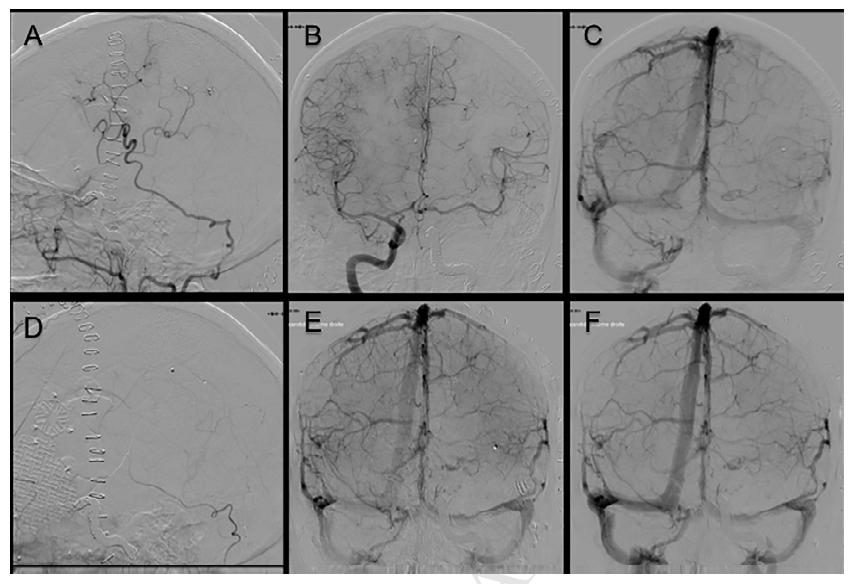

值得注意的是,肿瘤切除后1个月复查DSA显示搭桥流量较术前明显降低,但患者无任何临床症状(图7)。轻度肢体肌力减退逐步恢复,最终病情稳定出院,随访期间未见症状进展。

图7. 术后血管造影;A-C:搭桥术后1周造影示OA-MCA搭桥通畅。D-F:肿瘤切除术后1个月造影。整个术后过程中患者未出现新的神经功能障碍。